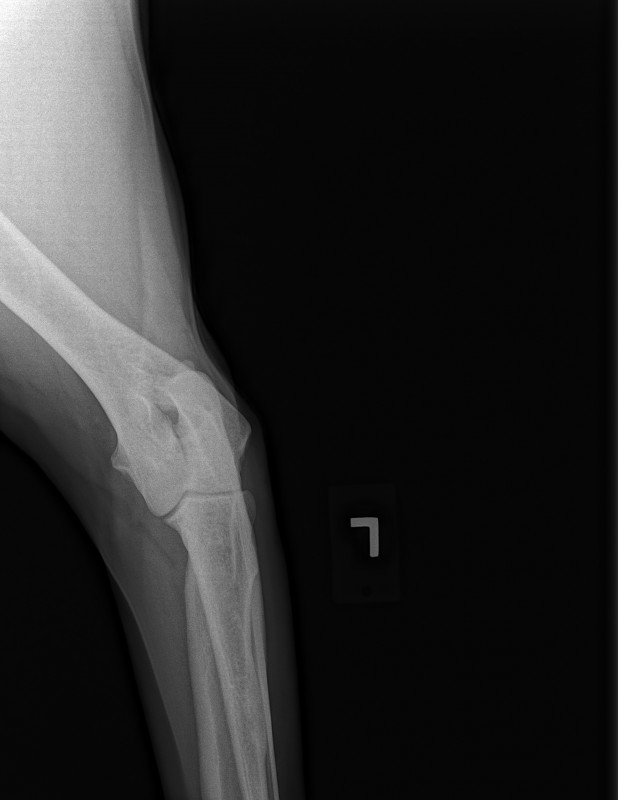

The current size of his mass is 8.2 cm x 10 cm x 21 cm. This is an extremely RARE cancer – less than 1%.

To further complicate matters, this mass has herniated down into his thigh and groin severely compromising his ureter and femoral nerve. He has had three CT scans of which his latest has shown that to date his chest remains clear of metastasis and his lymph nodes are not enlarged. His MRI has shown that his case is extremely complicated and the surgery he shall specifically require, scheduled for March 23rd has ONLY ever been done twice before by the two expert surgical oncologists assigned to him.